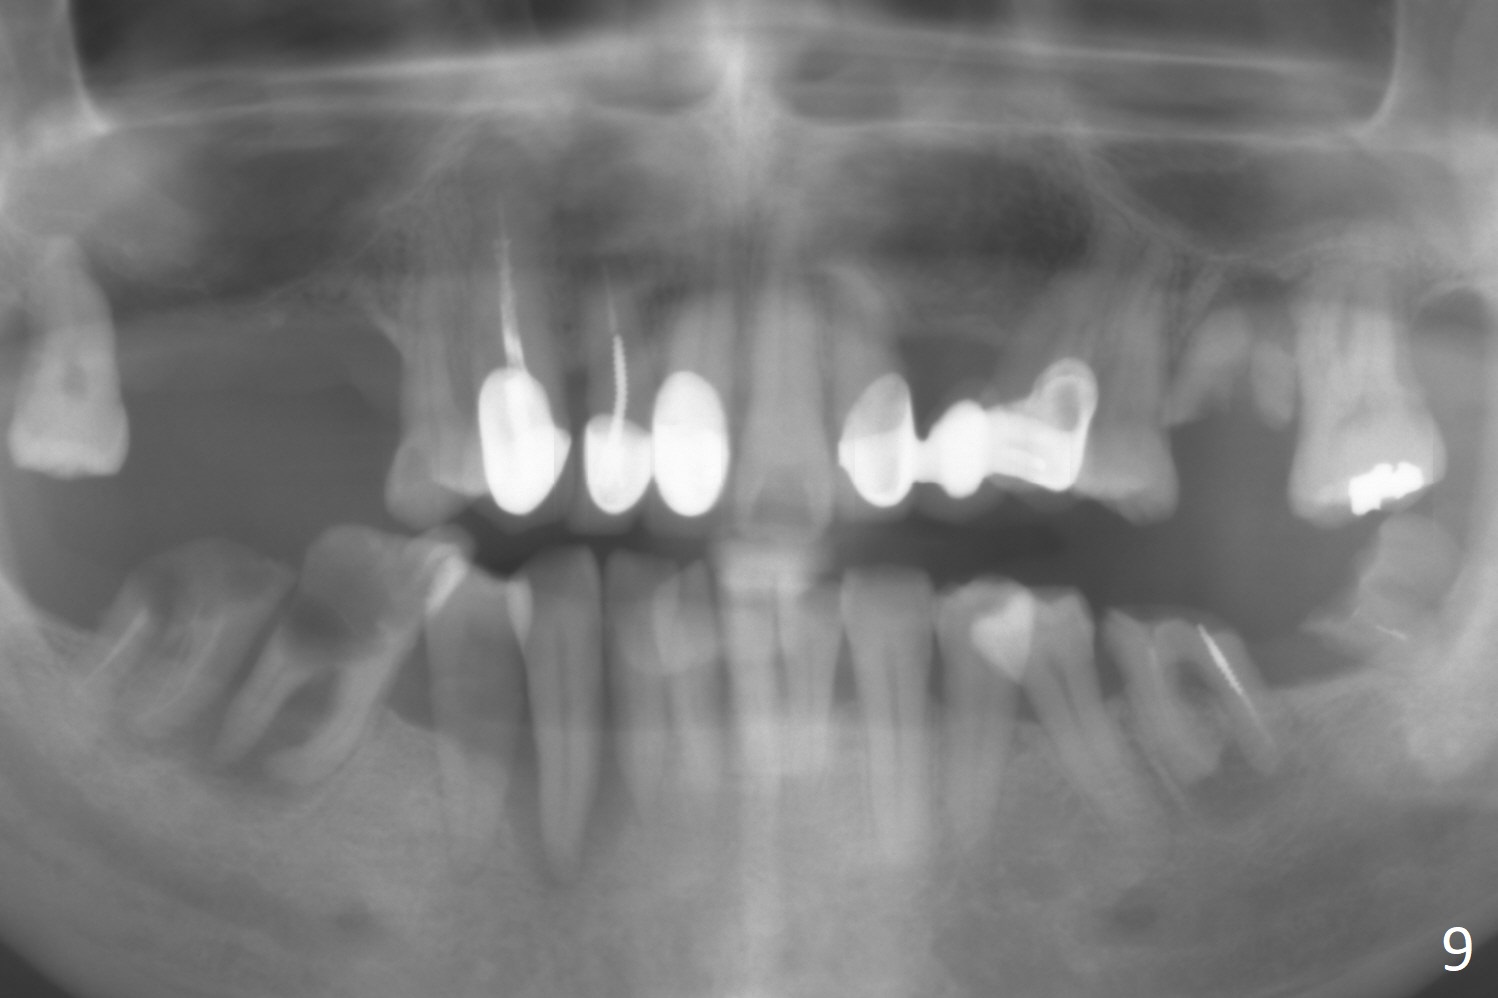

A 54-year-old man is 5 years post liver cancer surgery. After his platelet count returns normal, he wants to take care of his teeth. Most of his molars (#14, 19, 30,31) need extraction and implant placement (Fig.1-4). Although the 2nd premolars on the right are missing (Fig.1,3,4), it seems appropriate to establish 2 molar occlusion on the right (Fig.5,7,8) and 1 on the left (Fig.6,7 (because of #15 supraeruption (Fig.2 arrow))) . Since the residual roots in the lower right quadrant are irritating, implant placement will be done first (Fig.11, Clindamycin), followed by #2,3 (Fig.10) and 14(Fig.12 IBS) and 19 (Fig.12). Use IS drills and 4 and 5 mm stoppers to start osteotomy at #30 and 31, respectively.